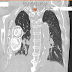

IMÁGENES DE PLOMBAJE TORÁCICO. UN PROCEDIMIENTO DE CASI UN SIGLO DE ANTIGÜEDAD EN EL TRATAMIENTO DE LA TUBERCULOSIS PULMONAR.

Se trata de un paciente masculino de 92 años de edad el cual acude por presentar hace una semana estreñimiento, reducción del estado gener...